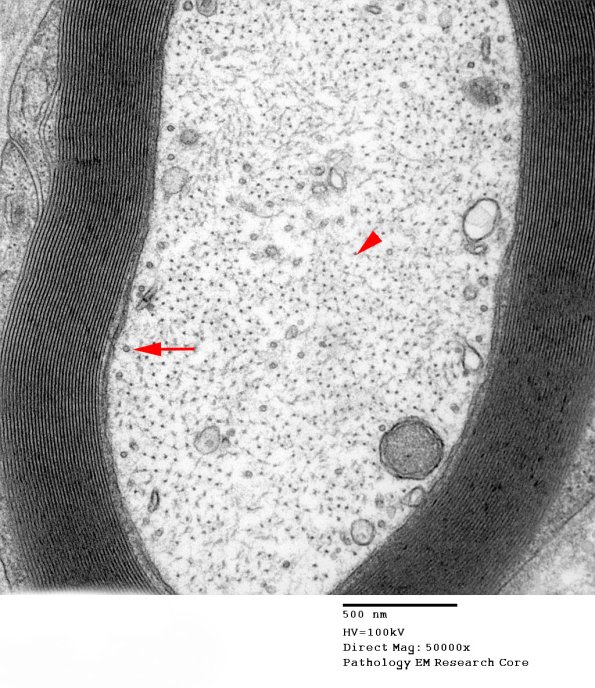

In a higher magnification image notice the beautiful periodicity of the myelin sheath as well as scattered microtubules (arrow) and relatively larger numbers of neurofilaments. (electron micrograph)